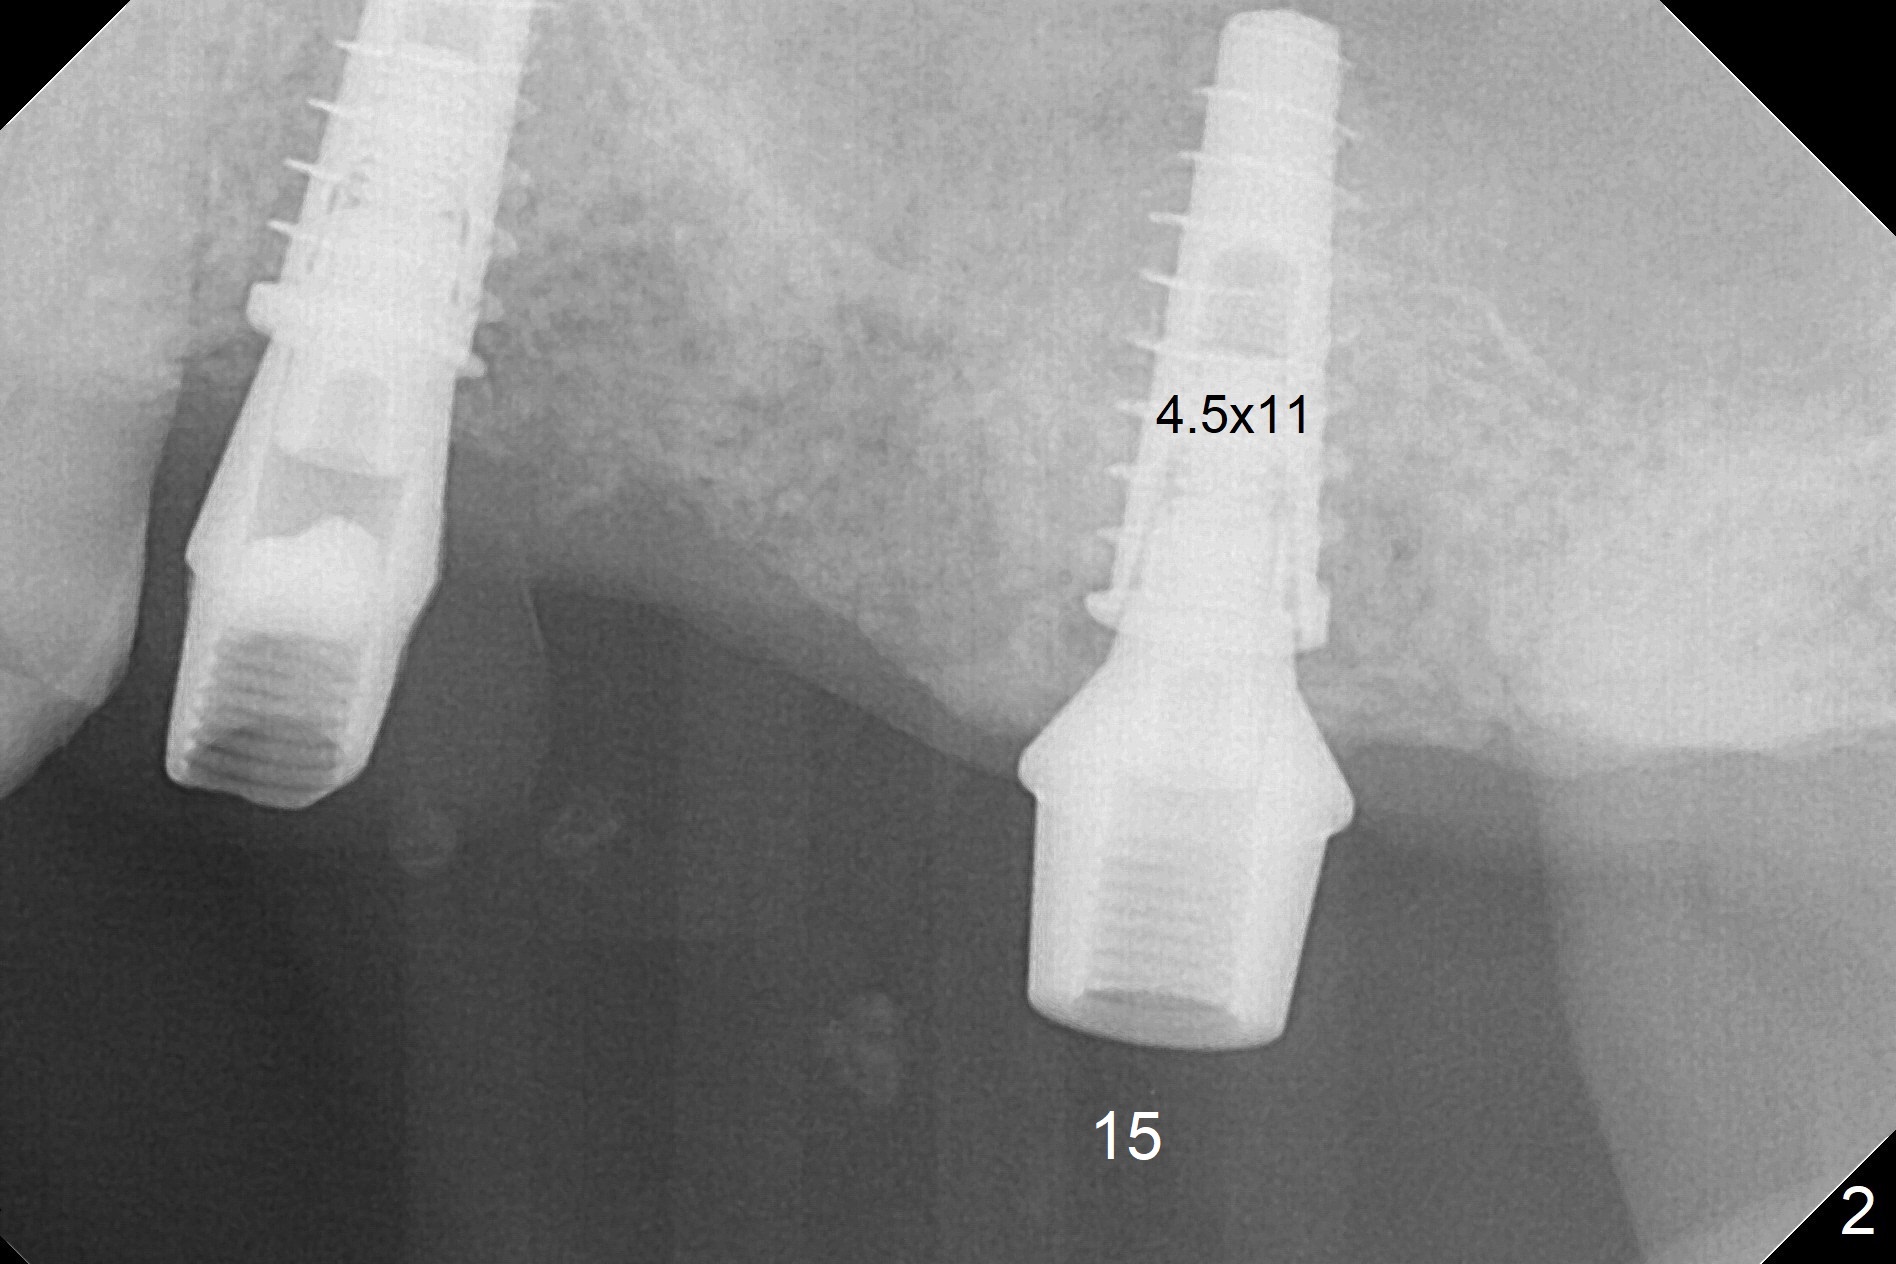

A fistula is found apical to #13 immediate implant 9 months postop (Fig.1).  It is curetted without bony defect.  Osteotomy at #15 is accomplished with traditional tapered osteotomes from 2 to 5 mm for 11 mm deep.  Although the patient is a little uncomfortable with tapping (as compared to Magic Expanders), a 4.5x11 mm dummy implant is placed 2 mm subgingival with primary stability (Fig.2).  Finally a 5x11 mm IBS implant (2 mm longer than the previous one) is placed with insertion torque > 50 Ncm; a 6x2 mm healing abutment is placed (Fig.3,4).  The advantages of the flapless surgery (because of the wide ridge) include no allograft or suture.  The fistula apical to #13 implant disappears 3 days postop (Fig.5), while the gingiva attaches to the healing abutment at #15 (Fig.6).